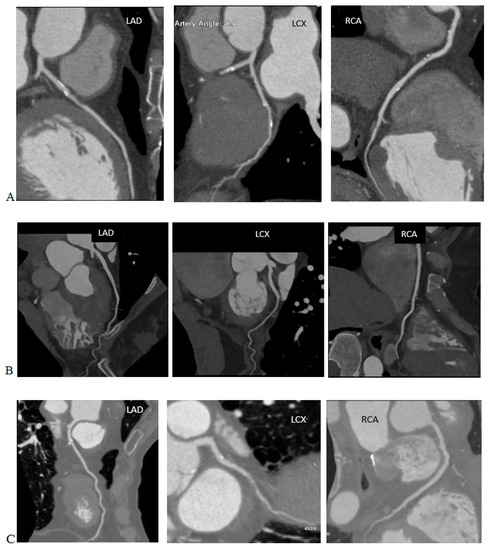

2.1. MSAD—Multiple Scan Average Dose

4.3. Iterative Image Reconstructions

4.4. Deep Learning-Based Image Reconstruction and Deep Learning-Based Image Denoising